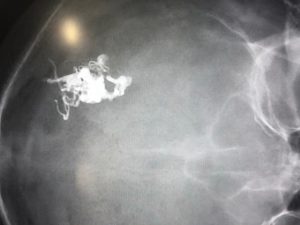

Com a presença do médico neurorradiologista Marco Túlio Rezende, de Belo Horizonte, o responsável pela área que atende tal especialização no Hospital, Dr. Robertson Pacheco, realizou o tratamento de um caso de malformação arteriovenosa (MAV) por meio de uma técnica diferenciada e atualizada de embolização. “Este procedimento destaca o poder inovador do centro médico e insere o serviço de neurorradiologia intervencionista do Hospital do Rocio no rol de serviços que buscam sempre o avanço científico e a versatilidade das técnicas utilizadas no tratamento endovascular das patologias vasculares intracranianas”, acrescenta Dr. Robertson Pacheco.